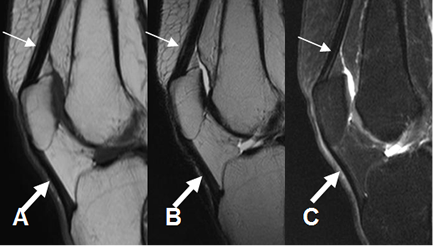

Los tendones de los diferentes grupos musculares, se aprecian como estructuras hipointensas en todas las secuencias. (Fig 5).

Fig 5. Señal normal del tendón.

A: RM sagital en T1, B: RM sagital en T2 y C: RM sagital en STIR. Mecanismo extensor hipointenso en todas las secuencias. Tendón del cuadriceps (Flecha delgada) y tendón patelar (Flecha gruesa).